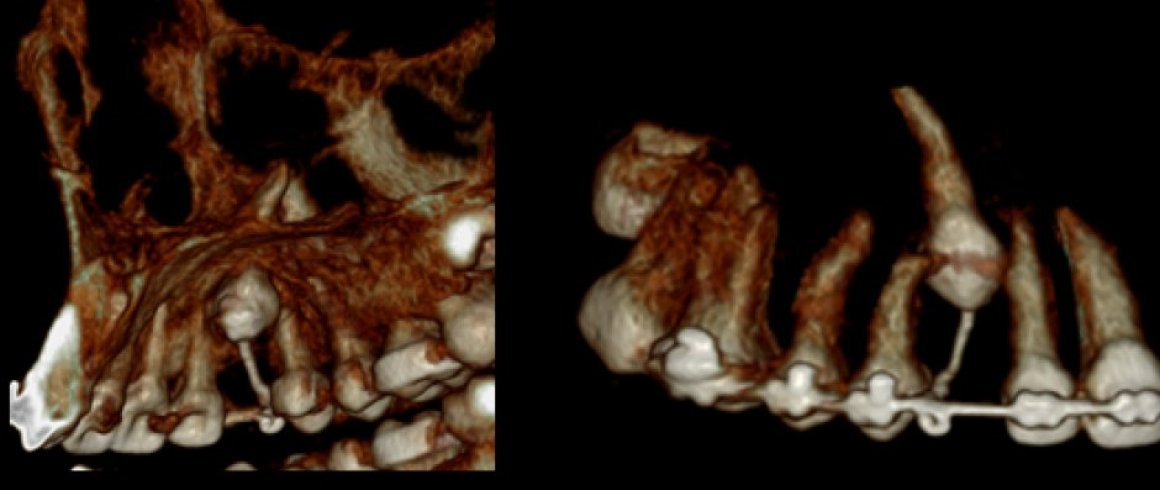

- Tomografía

- Localización de Diente Impactado